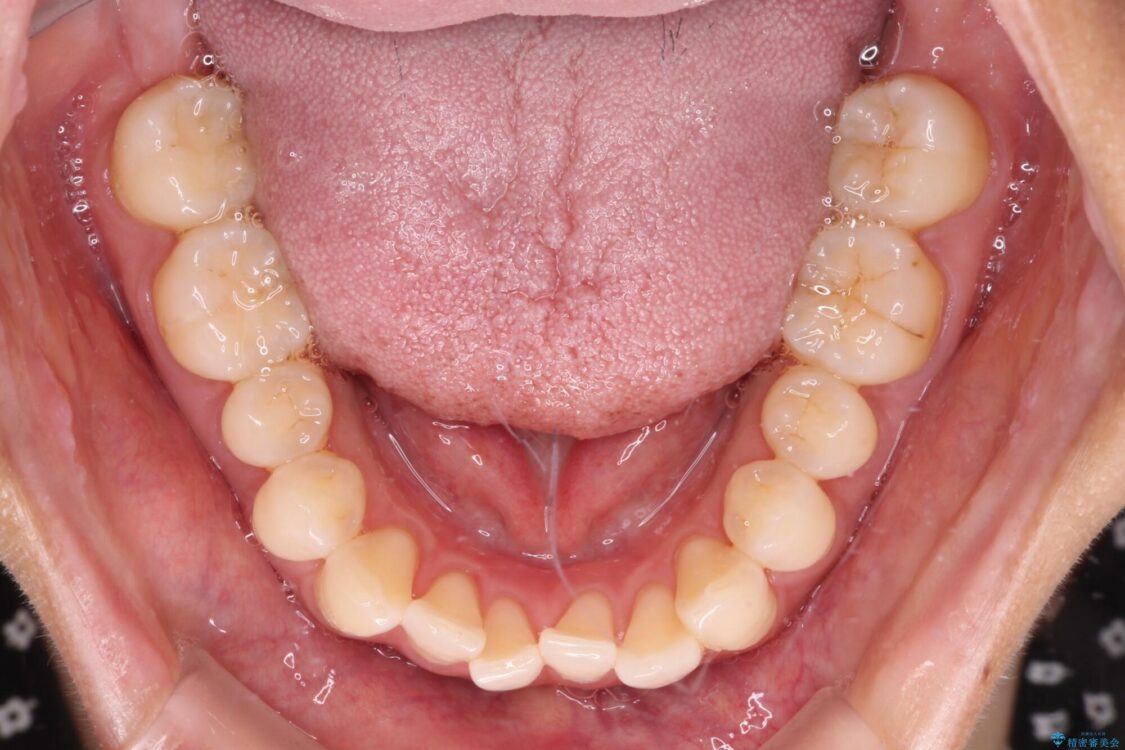

前歯のデコボコで前方に出ていることを気にして来院された患者様です。

上顎前歯が捻れて前方に飛び出しており、下顎前歯もそれに沿うようにデコボコとなっていました。

IPR(歯と歯の間を削る処置)によりスペースを獲得して上下顎前歯のデコボコを改善し、飛び出している前歯が引っ込むように設定し、インビザラインにて矯正治療を行うこととしました。

• 【モニター】前歯のデコボコをインビザラインで改善 治療前画像